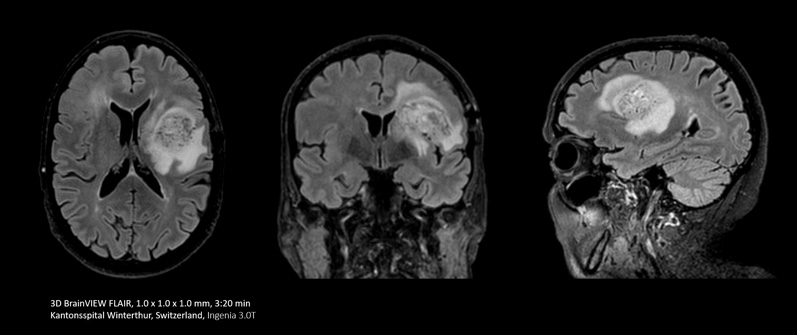

With Compressed SENSE you can replace your single orientation 2D FLAIR scan with a multi-orientation 3D volumetric FLAIR scan in only 3 and a half minutes scan time.

I do a lot of brain imaging, and we used to do the FLAIR sequence using a 5 mm thick slice. Now with Compressed SENSE we are able to take a 3D volumetric scan for about 6 minutes down to maybe 3 and a half minutes.”

Dr. Mark Oswood, MD, PhD, Neuroradiologist, Hennepin Healthcare, Minneapolis, USA